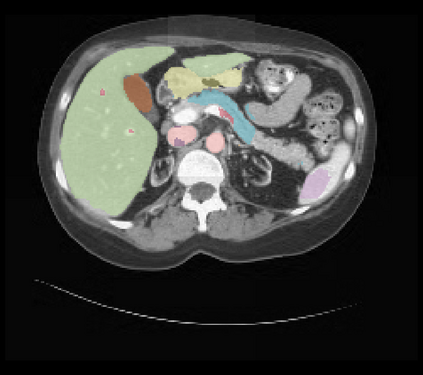

It is imperative to ensure the robustness of deep learning models in critical applications such as, healthcare. While recent advances in deep learning have improved the performance of volumetric medical image segmentation models, these models cannot be deployed for real-world applications immediately due to their vulnerability to adversarial attacks. We present a 3D frequency domain adversarial attack for volumetric medical image segmentation models and demonstrate its advantages over conventional input or voxel domain attacks. Using our proposed attack, we introduce a novel frequency domain adversarial training approach for optimizing a robust model against voxel and frequency domain attacks. Moreover, we propose frequency consistency loss to regulate our frequency domain adversarial training that achieves a better tradeoff between model's performance on clean and adversarial samples. Code is publicly available at https://github.com/asif-hanif/vafa.